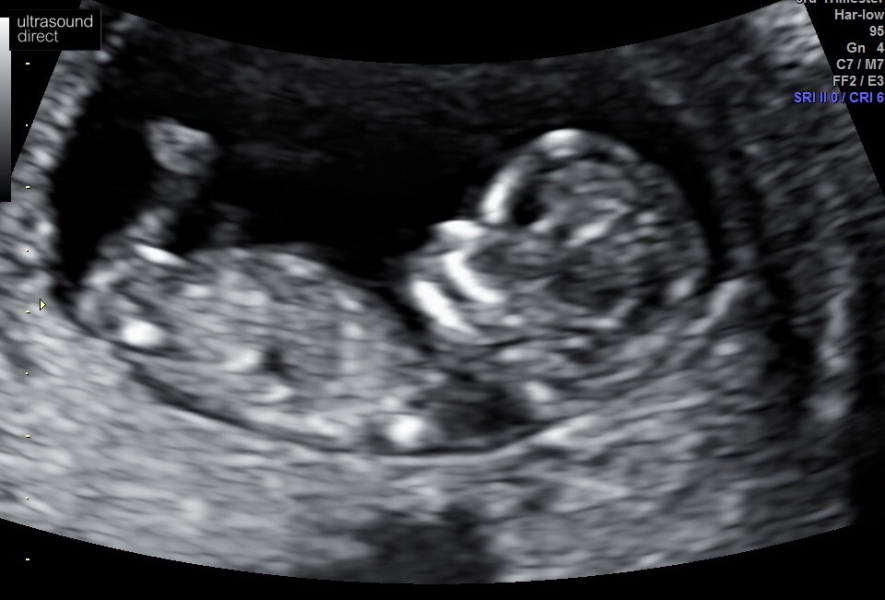

Had another scan today for peace of mind before Christmas and my 12 week scan on the 4th. Baby was moving around so so much and their heartbeat was strong 💕

Measuring a little behind but they said that can be normal and bean was probably scrunched up! 🙏